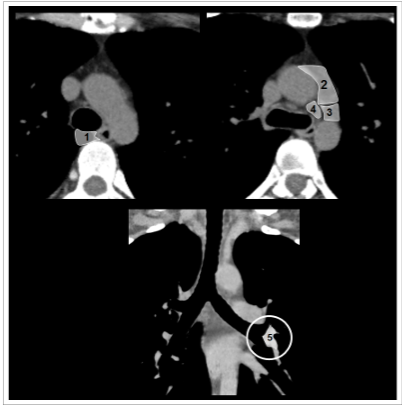

Analise as imagens a seguir.

Os métodos de imagem são fundamentais para diagnóstico e estadiamento de neoplasias pulmonares, sendo fundamental a denominação correta das cadeias linfonodais mediastinais. A nomenclatura correta dos níveis linfonodais exemplificados é a seguinte: